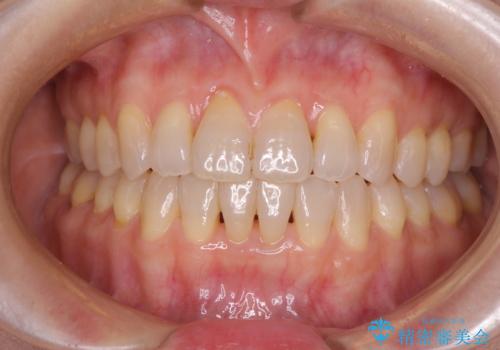

- 虫歯が多く、セラミッククラウンにより虫歯治療を行っている途中で矯正治療をしたいとのことで来院された患者様です。

上顎前歯が舌側に転位しており、なるべく早く楽に矯正したいとのことで、ワイヤー矯正を行うこととしました。

インビザライン矯正では苦手とする舌側転位した前歯をスムーズに改善することができました。

矯正治療により歯磨きがしやすくなったので、虫歯予防のセルフケアが行いやすい環境となりました。